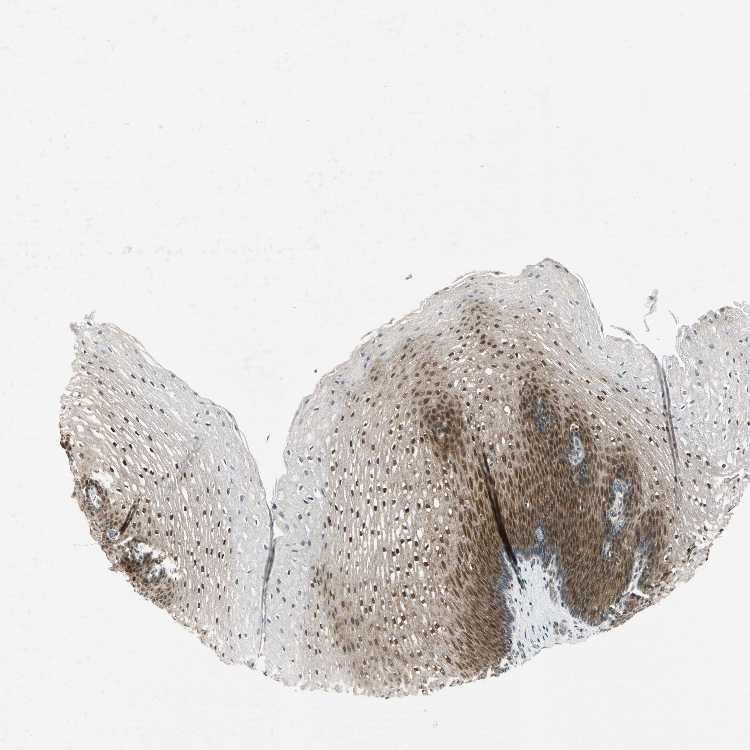

ESOPHAGUS - Antibody stainingi

Antibody staining in the annotated cell types in the current human tissue is reported as not detected, low, medium, or high, based on conventional immunohistochemistry profiling in selected tissues. This score is based on the combination of the staining intensity and fraction of stained cells.

Each image is clickable and will lead to virtual microscopy that enables deeper exploration of all samples and also displays staining intensity scores, fraction scores and subcellular localization as well as patient and tissue information for each sample.

Antibody HPA010010Antibody CAB019404

Squamous epithelial cells HighMedium